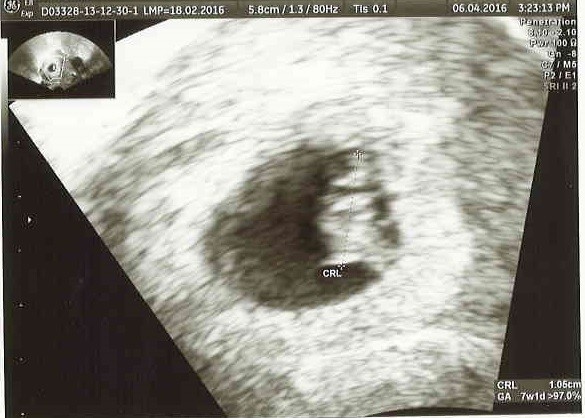

I po wizycie ... :) Mój mały człowieczek ma 11mm, serducho mu wali, że ho ho :) W końcu trochę ze mnie zeszło, a nosiło mnie od samego rańca. Przedstawiam Wam mojego ludzika :)

usg.jpg

67,4 KB · Wyświetleń: 525